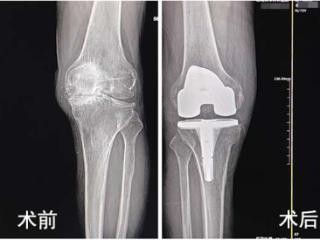

从步履维艰到大步行走,济南关节外科医院帮七旬老人告别膝关节炎